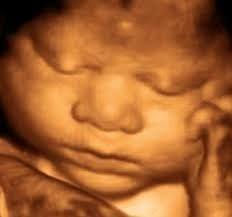

"A ecografia 4D é uma experiência única e inesquecível que fará com que se sinta ainda mais mãe.

São muitos os artigos que falam dos benefícios e da utilidade emocional para os futuros pais graças a poderem ver com nitidez o seu futuro bebé. O nível de consciencialização da gravidez e a sua implicação aumenta, já que às vezes necessitamos ver para sentir.

Longe das clássicas ecografias 2D onde quase não se aprecia o bebé, o Ecox4d permite-lhe ver a carinha do seu menino ou menina com a melhor qualidade de imagem, graças a texturas suaves e delicadas.

Escutará o seu batimento do coração, verá como se ri, se esconde, joga dentro da sua barriga, boceja ou se chucha o dedo. Um momento único que ainda pode partilhar com a sua família e amigos.